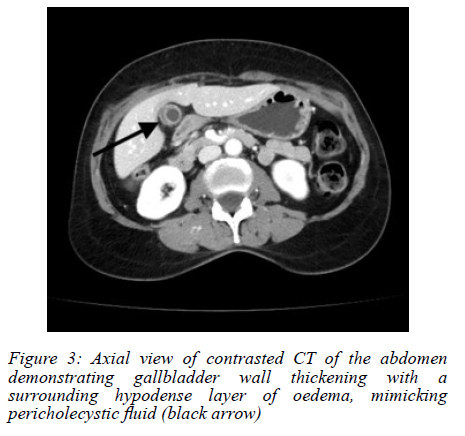

An abdominal ultrasound (AUS) showed a possible stone in the gallbladder neck, with a thickened and oedematous gallbladder wall (Figure 1). No masses were noted on sonar. The history of loss of weight was further investigated. A colonoscopy was performed, which was normal. A computed tomography (CT) scan did not show any concerning features, and a thickened gallbladder wall was once again visualised (Figure 2, 3).

Radiologically, CT and ultrasound findings are nonspecific, ranging from wall thickening to mass-like lesions with necrosis or calcification.68 These features overlap significantly with gallbladder malignancy or chronic inflammation,6,8 making preoperative diagnosis challenging. Radiologic "red flags" suggesting TB over carcinoma include gallbladder wall with necrotic core, multiple flecked calcifications, broad-based micronodular lesions, pericholecystic oedema, and necrotic lymph nodes.6 Consequently, in the absence of systemic TB features or pulmonary symptoms, most diagnoses hinge on postoperative histopathology, where necrotising granulomas with or without acid-fast bacilli confirm the diagnosis.9